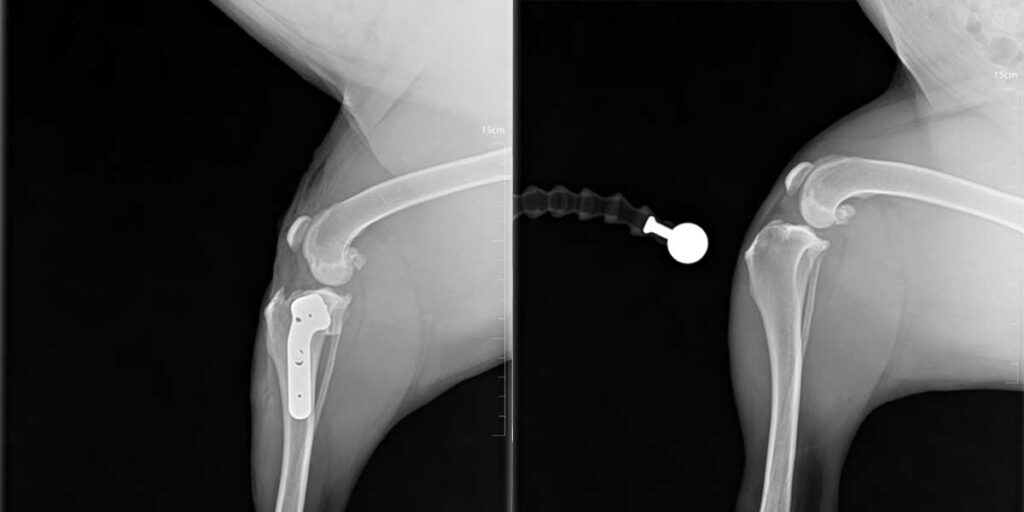

Dijagnoza se postavlja rendgenskim snimkama koje pokazuju lokaciju i tip prijeloma.

Liječenje može biti konzervativno, pomoću gipsa ili udlage, ili kirurško, uključujući pločice, vijke, čavle ili vanjsku fiksaciju.

Kirurško liječenje omogućuje precizno poravnanje kostiju i stabilnost tijekom cijeljenja, što skraćuje vrijeme oporavka.